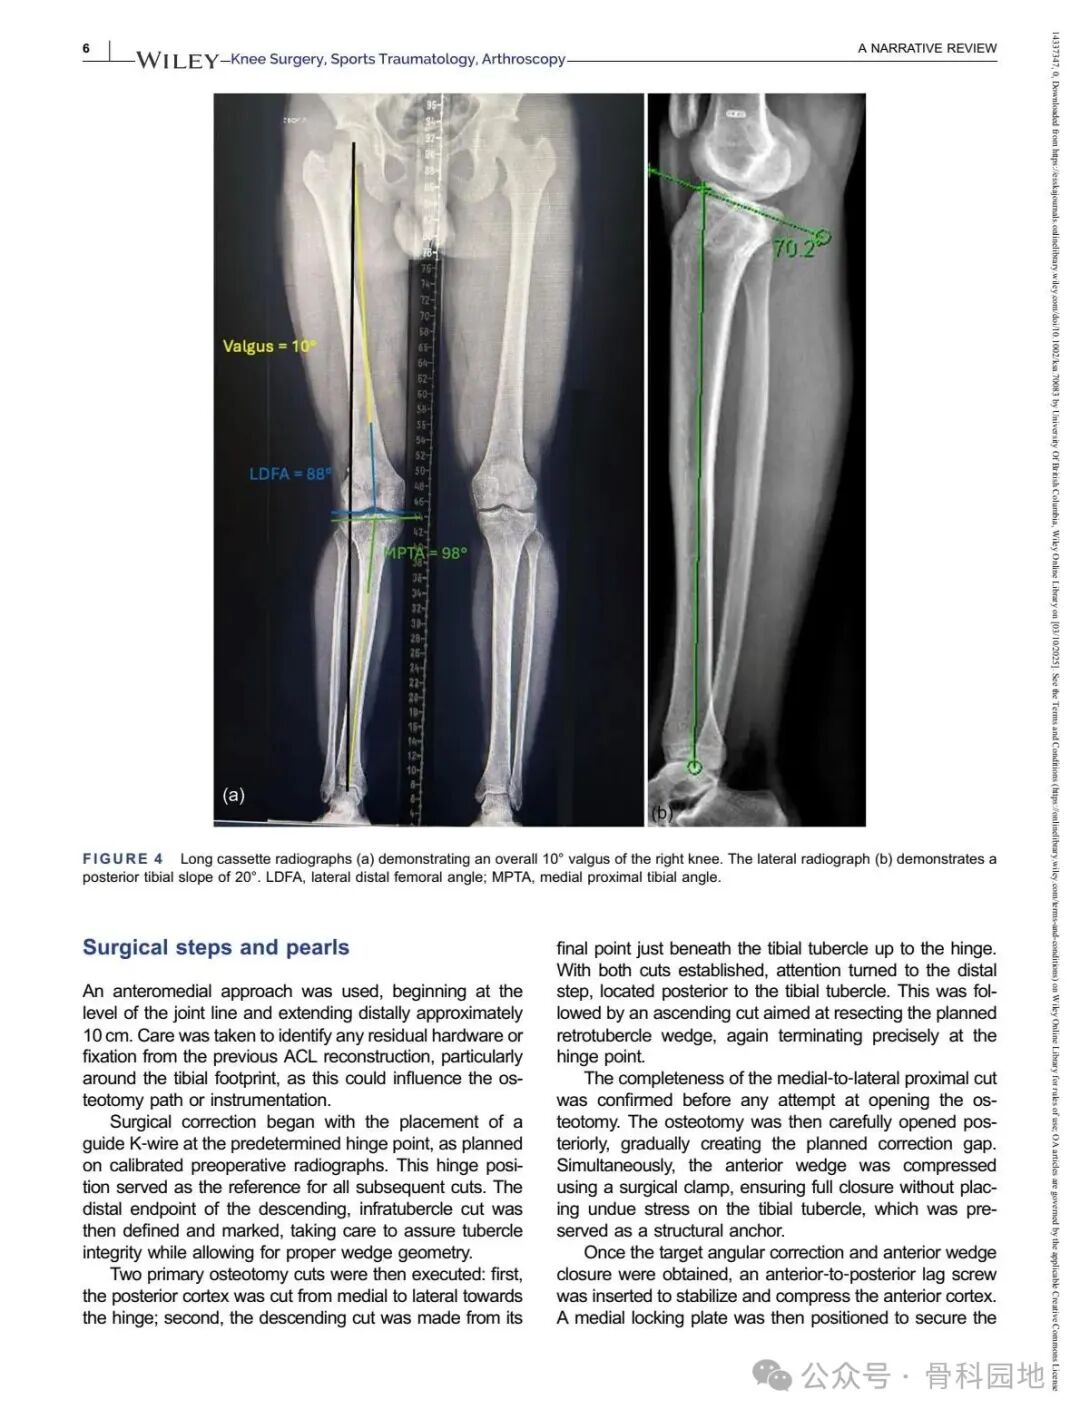

Although conventional high tibial osteotomy (HTO) primarily addresses coronal plane malalignment, the importance of sagittal plane alignment—specifically the posterior tibial slope (PTS)—cannot be overlooked in the setting of cruciate ligament insufficiency. Combined coronal and sagittal plane deformities are relatively rare and present unique surgical challenges. This narrative review summarizes the available literature and presents technical tips for managing complex biplanar deformities through a case‑based discussion of different techniques.